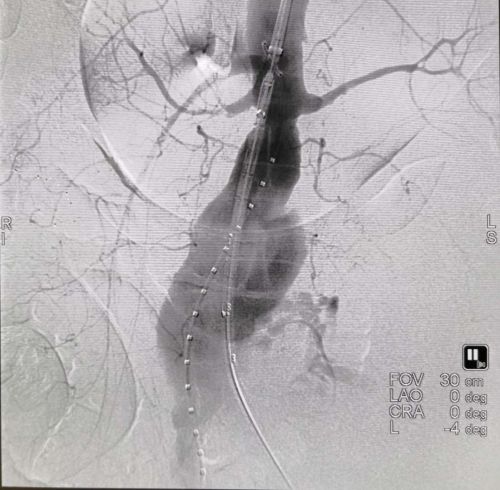

腹主动脉破裂出血。

覆膜支架腔内完美修复破裂瘤体。

谁知,刘某刚躺上手术台便突发腹主动脉瘤二次破裂,血压趋于零,生命危在旦夕。在大剂量的升压药和快速输血情况下,血压勉强维持在60/40mmHg,情势仍然十分危急。王庆带领该院介入血管外科团队在20分钟内完成复杂的腔内修复治疗,出血立即停止,患者生命体征趋于稳定。